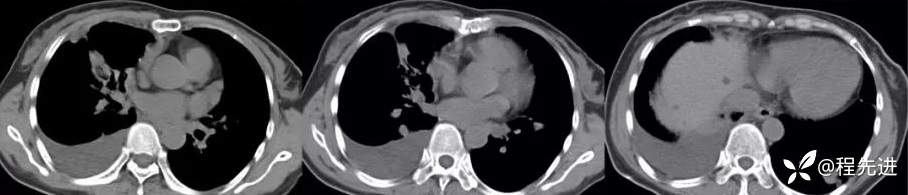

纵隔窗

增强动脉期